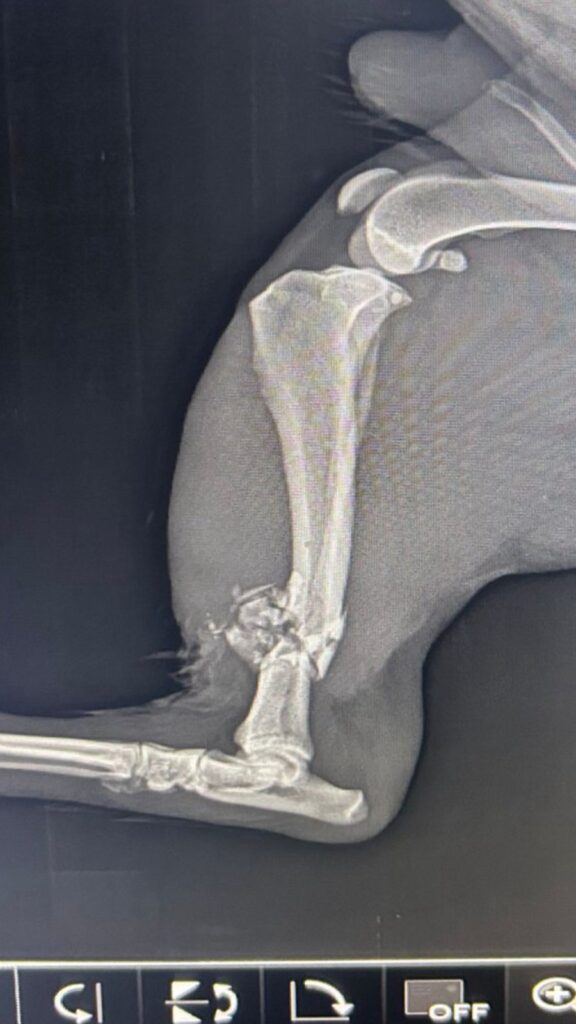

De acuerdo con testimonios recabados en la zona, el perro identificado como “Hachi” por residentes locales, recibió al menos dos disparos en las extremidades traseras, Dispaos que aseguran, provienen de armas de elementos de la Guardia Nacional que se desplazaban en una patrulla, según consta en una video grabación.

Según reportes médicos, el estado de salud del animal es delicado y requiere una cirugía ortopédica para recuperar su movilidad.